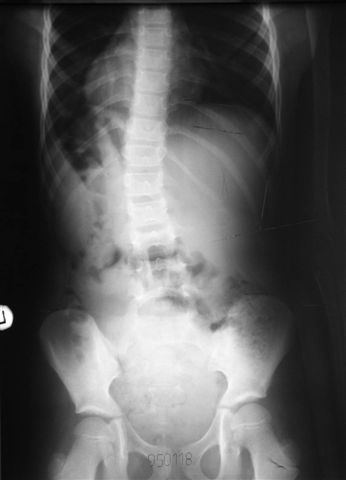

Na radiogramach przebieg leczenia jednej z moich pacjentek.